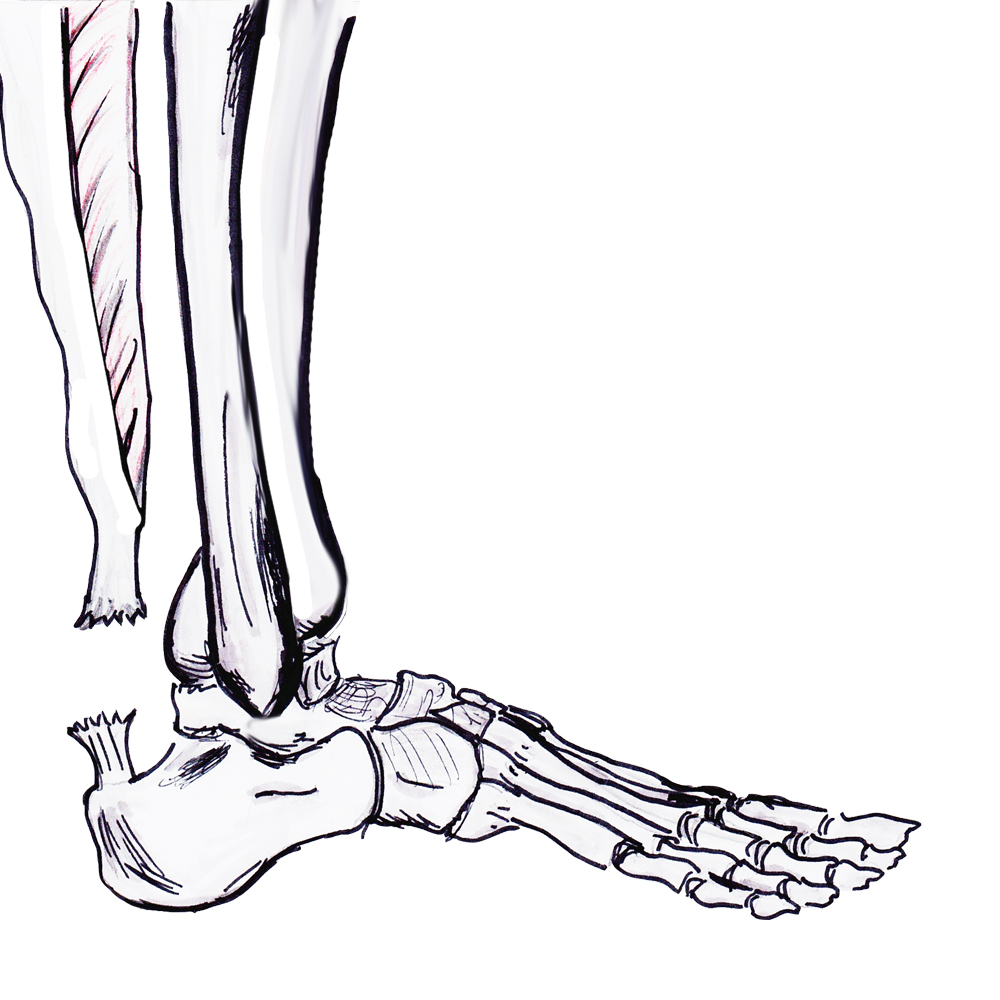

Anatomy

Gastrocneumic and soleus tendon

- longest tendon in human body

- fibres spiral 90° before inserting on superior calcaneal tuberosity

- medial gastrocs inserting posteriorly

- allows elastic recoil & energy storage

Paratenon

Blood supply

- paratenon

- small amount muscle proximally and calcaneum distally

- watershed area 2 - 6 cm proximal to calcaneal tuberosity / area of rupture

Plantaris

- present in 90% population

- medial to Tendo-achilles